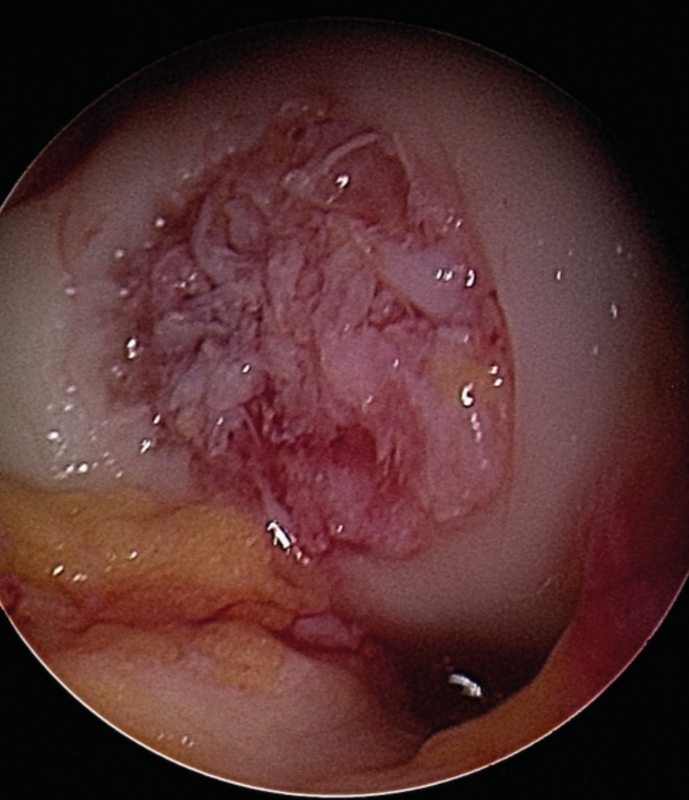

For the M-ACT it is recommended in clinical practice to compile the consent forms and any reporting to the chondrocyte registry in advance and to arrange the harvesting and implant dates with the patient directly according to the cell expansion time. During the first procedure an arthroscopy is performed to confirm the indication and the defect is debrided thoroughly (Fig. 25).

Chondrocyte harvesting is performed after careful defect documentation. The cells can be cultivated in gel form, membrane associated for suture fixation or as spheroids. Depending on the system, cartilage biopsies are harvested for cell cultivation (e.g. 2−3 small cylinders), usually from the cranial notch (Fig. 26). The biopsy cylinders are sent for cultivation. This is followed by the realignment osteotomy in the same session.